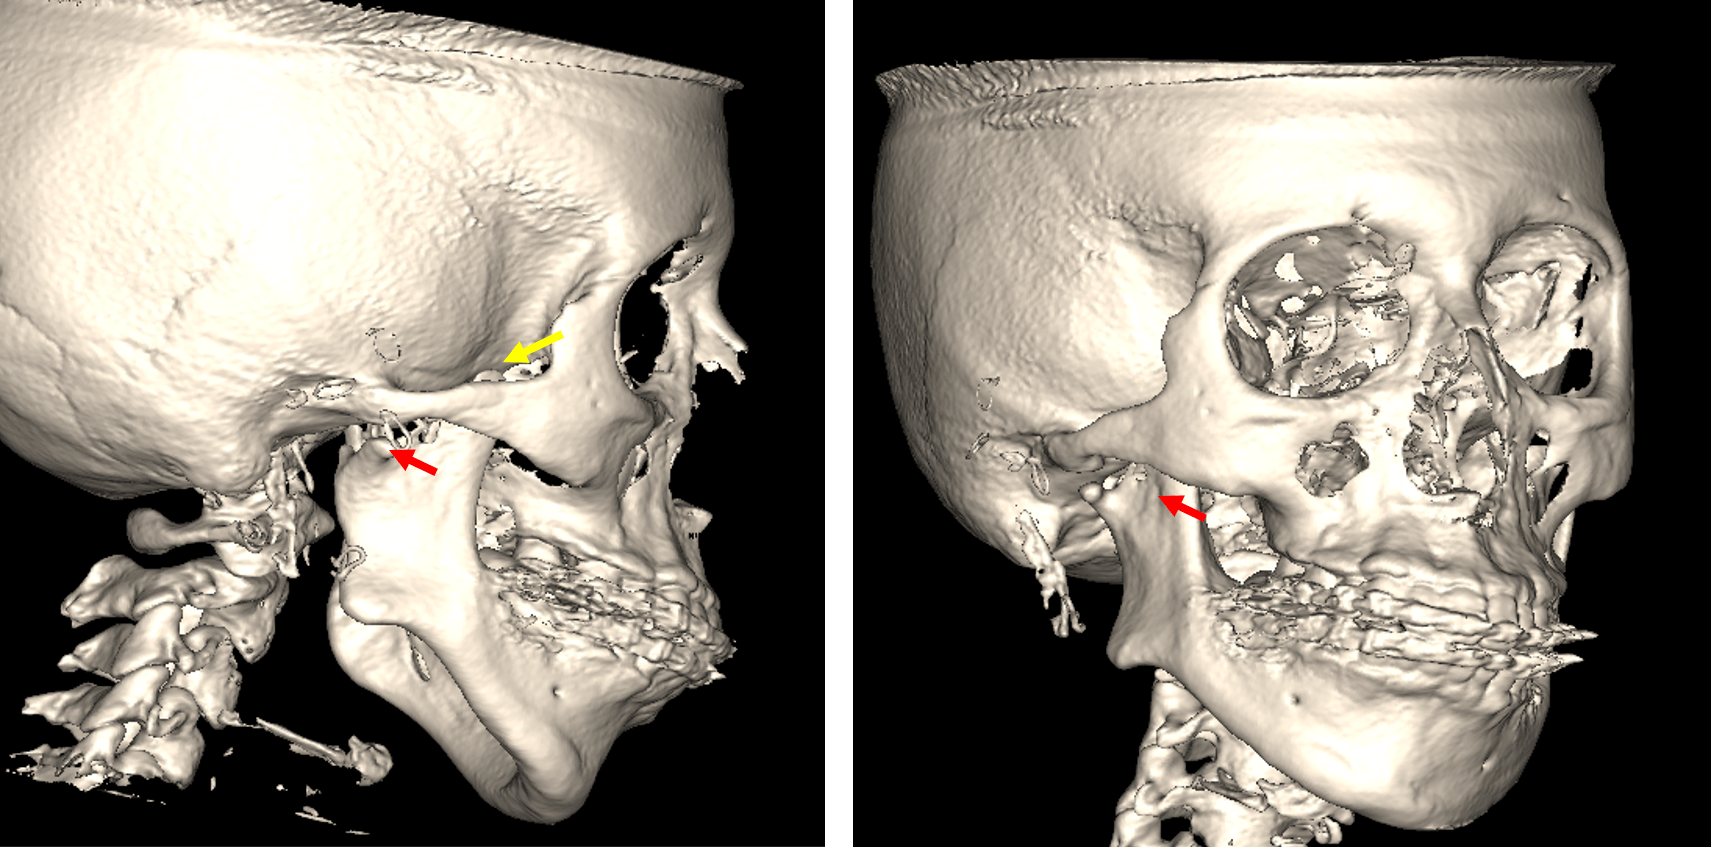

Fig.5

En la reconstrucción tridimensional (Fig.5) se observa la hipoplasia del cóndilo mandibular del lado derecho (flecha roja) y la hiperplasia de la apófisis coronoides del mismo lado (flecha amarilla).